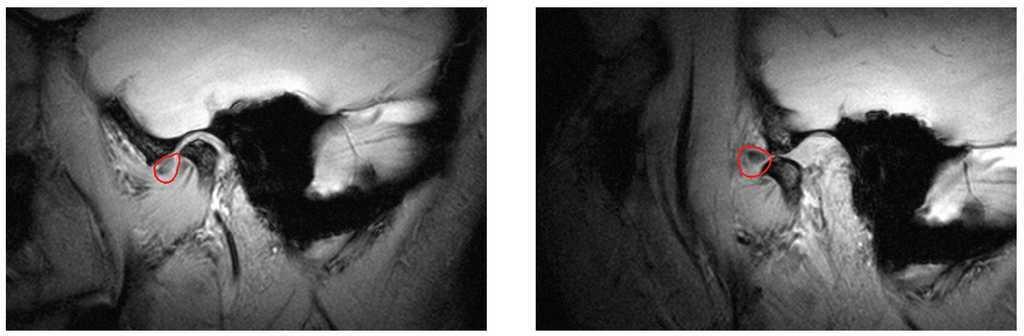

Desplazamiento discal anterior sin reducción (fig. 8)

Figura 8. Desplazamiento discal anterior sin reducción (disco enmarcado en rojo) (izquierda: boca cerrada, derecha: boca abierta). Este tipo de desplazamiento se caracteriza en la fase aguda por dolor y disminución de la movilidad mandibular. En estadio crónico, el paciente puede estar asintomático, pero es posible desencadenar estos síntomas mediante determinadas maniobras.

El disco se coloca en estos casos por delante del cóndilo tanto con la boca abierta como con la boca cerrada. La apertura puede estar limitada en la fase aguda y todo intento de forzar más la apertura puede provocar dolor. Además, al abrir la boca, la mandíbula se desvía hacia el lado afectado. Desde el punto de vista terapéutico, las opciones son limitadas y ninguna de ellas es curativa. Se dispone, por un lado, de procedimientos invasivos13, cuya eficacia además es discutible y, por otro lado, de procedimientos no invasivos como el tratamiento con férulas22.

Debido a la situación de desplazamiento anterior permanente del disco, la evolución de la sintomatología depende en gran medida de la capacidad de adaptación de las estructuras de la ATM.

Curiosamente, muchos de los pacientes con desplazamiento discal anterior sin reducción no presentan ninguno de los síntomas descritos20. Durante la entrevista para obtener la anamnesis, y también mediante cuestionarios específicos, se pueden recoger datos importantes sugestivos de la existencia de un desplazamiento discal anterior sin reducción (como una apertura bucal limitada en el pasado). Esto subraya la importancia de prestar especial atención a la anamnesis.

En ausencia de sintomatología, indudablemente no hace falta una intervención terapéutica, pero es posible que este grupo de pacientes desarrolle más frecuentemente molestias después de una rehabilitación protésica. Los pacientes deben ser informados de esta posibilidad si se identifican datos positivos en la anamnesis.